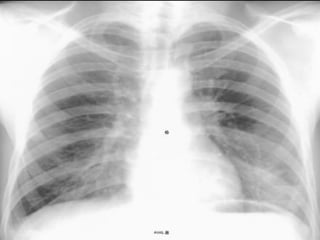

A cavity is > 1cm

in diameter, and its

wall thickness is

more than 3 mm.